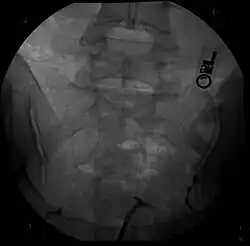

![]() Macica dwurożna | |

- histerosalpingografię (HSG)